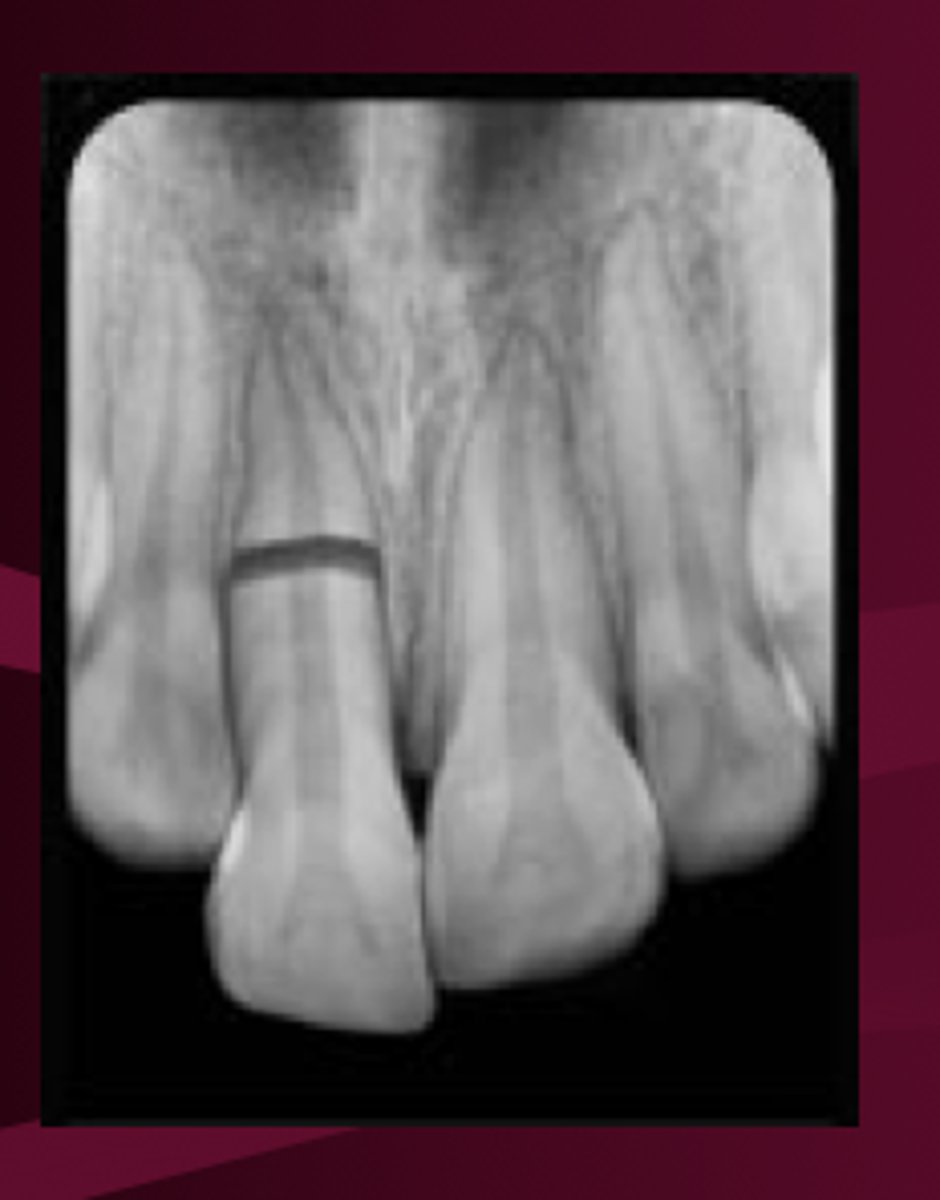

Root Fracture

coronal fragment may be mobile and may be displaced

occlusal interference may be present

What is the poorest prognosis for root fracture?

coronal

_% of primary tooth injuries are rooth fractures

2-4%

___% of teeth with root fracture exhibited pulpal necrosis

9.4%

___% of teeth with root fracture exhibited pulp obliteration

9.2%

Root fractures are usually the ___ to -__

middle to apical 1/3

T/F: Treatment must occur if there is coronal fragment displacement

FALSE